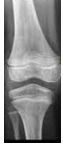

“A ossificação endocondral inicia-se sobre uma peça de cartilagem hialina do esqueleto que irá formar tecido ósseo” (MCARDLE, KATCH & KATCH, 2019).

Observe a imagem e responda qual o nome da estrutura indicada.